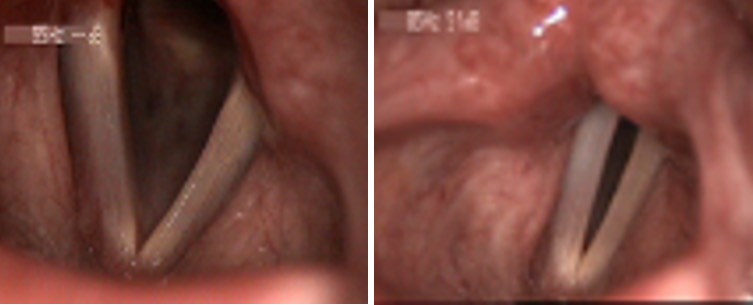

2601. Данная ларингеальная картина характеризует